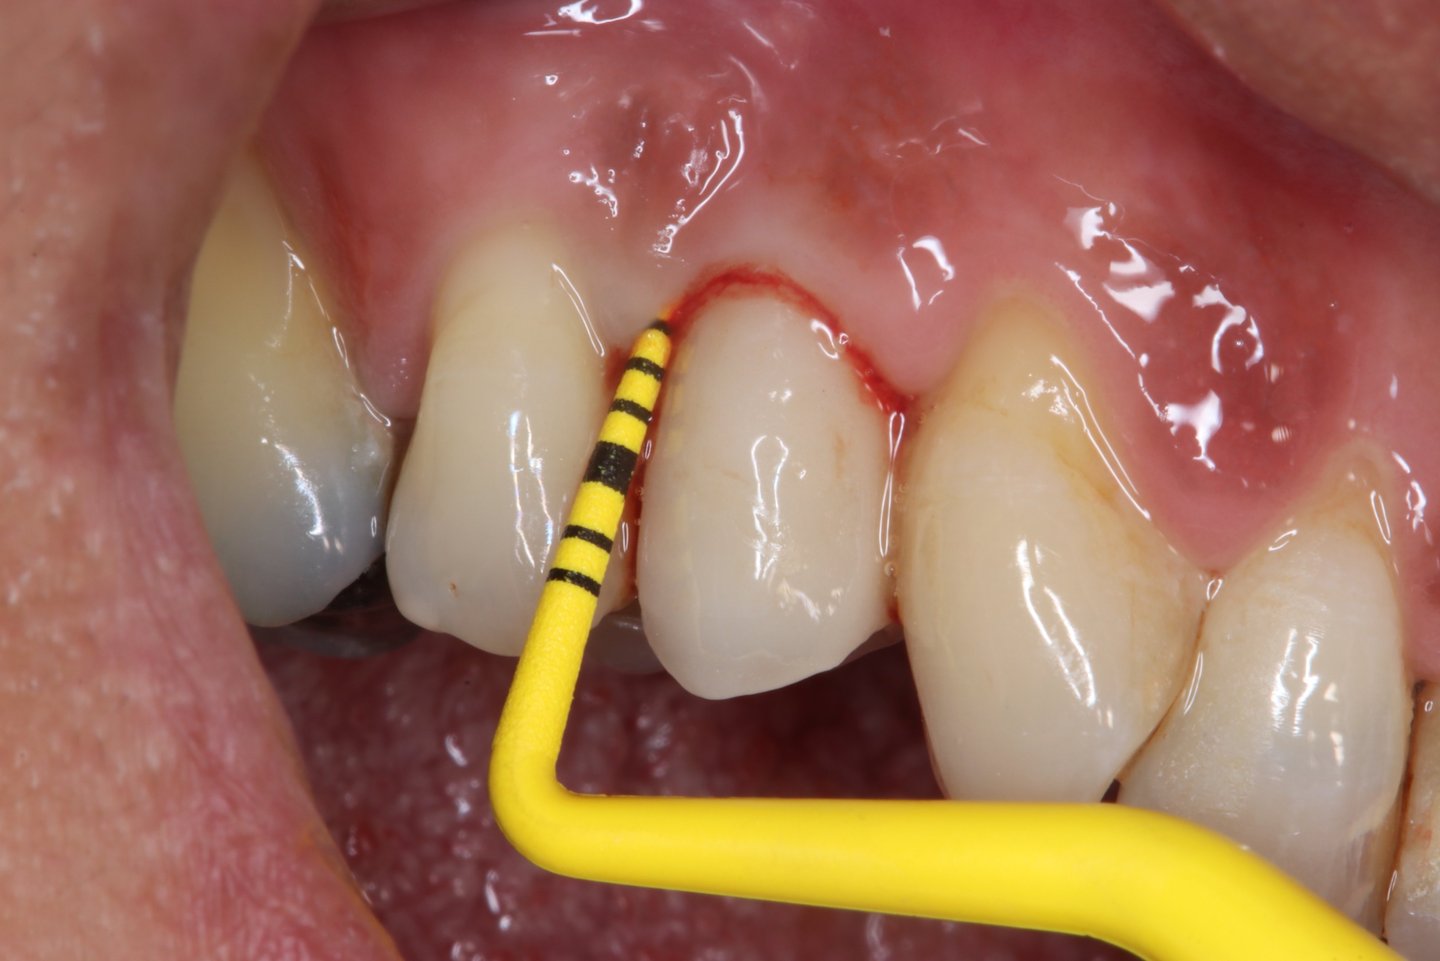

Chirurgie muco-gingivale

Traitement des récessions gingivales